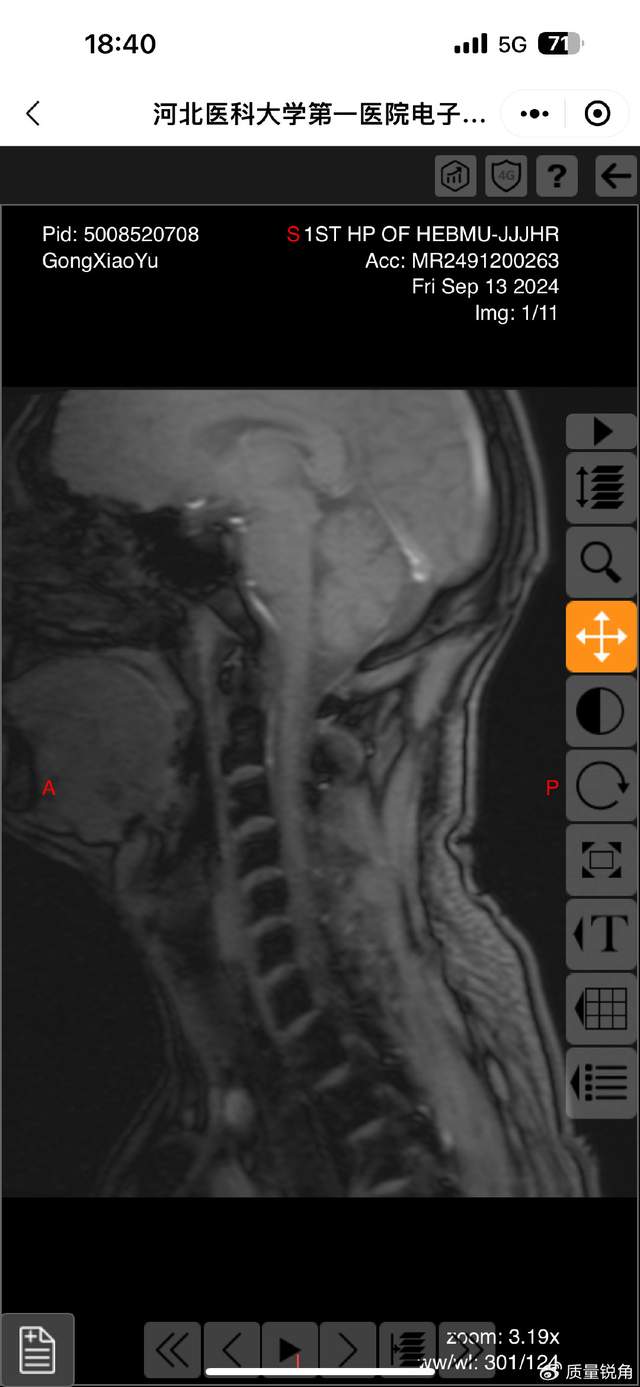

这起纠纷的源头是一场普通交通事故。原告龚小玉诉称,事故导致自己颈椎、腰骶骨折,向法院提交了病历、司法鉴定报告等证据,主张赔偿。但叶某团队手中,却持有龚小玉事发后发送的医疗影像资料。“我们找了三位骨科专家会诊,影像里只有骨质增生,没有任何新鲜或陈旧骨折的痕迹。”叶某表示,一审、二审中,他们多次提交该影像证据,并当庭请求法院责令龚小玉出示原始骨折影像——这是人身损害赔偿案件中证明伤情的核心直接证据。

可关键是,龚某玉之前发给叶某他们手里的医疗影像清清楚楚,只有骨质增生,压根没骨折啊!二审时找医生看CT,医生也说“看不清”骨折痕迹,叶某他们还向石家庄市中级法院说了,只要龚某玉拿出真实骨折影像,立马无条件赔偿,结果法院根本不理!